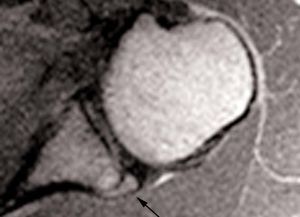

POLPSA (posterior labral periosteal sleeve avulsion)

Esta lesión se asemeja a la ALPSA, pero ocurre en el borde glenoideo posterior. El LG se halla desplazado hacia dentro y por detrás del borde glenoideo posterior. El mecanismo de producción del POLPSA es una dislocación posterior, y por tanto se puede encontrar también un Hill Sachs invertido19 (fig. 14).

. Artrorresonancia axial T1 con supresión grasa donde se observa una rotura del labio glenoideo posterior con desplazamiento posteromedial (flecha). Nótese la situación del labio glenoideo en comparación con una rotura sencilla, no desplazada, que se observa en la figura 13. Obsérvese la presencia de una lesión de Hill-Sachs invertida (cabezas de flecha), en relación con una dislocación posterior con reducción.Lesión de Bennett